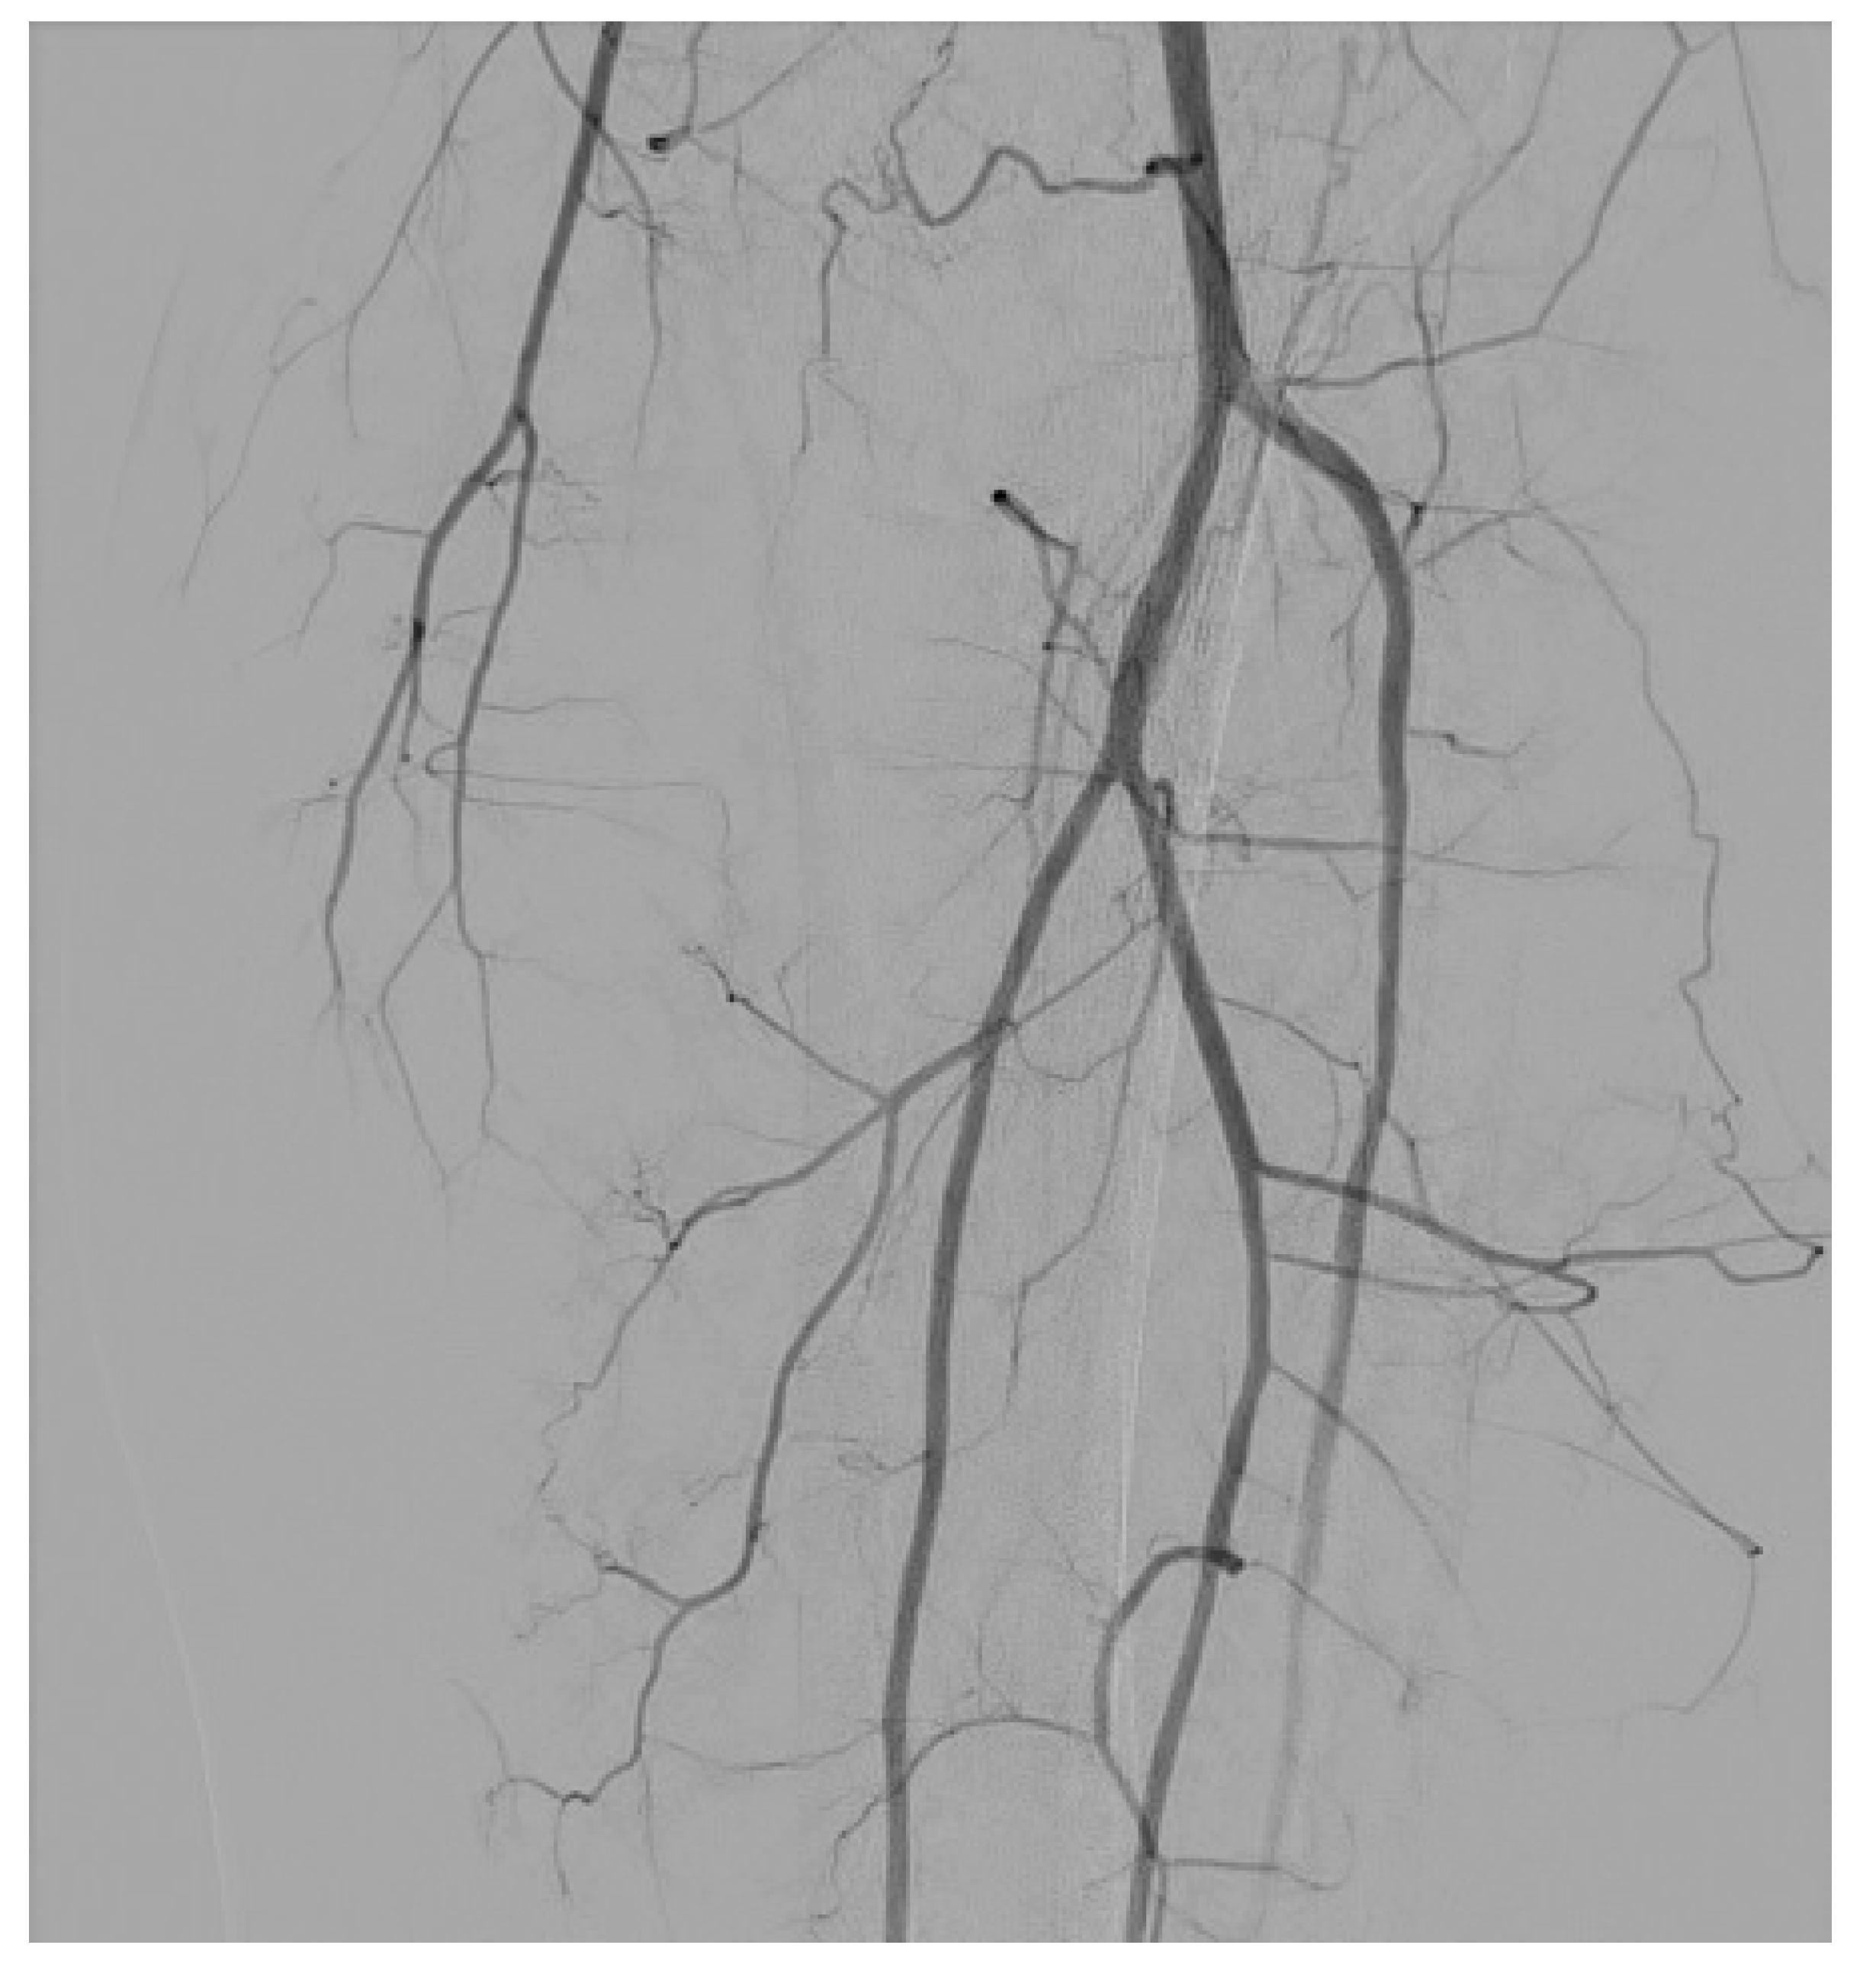

3.3. Arteriovenous Fistula